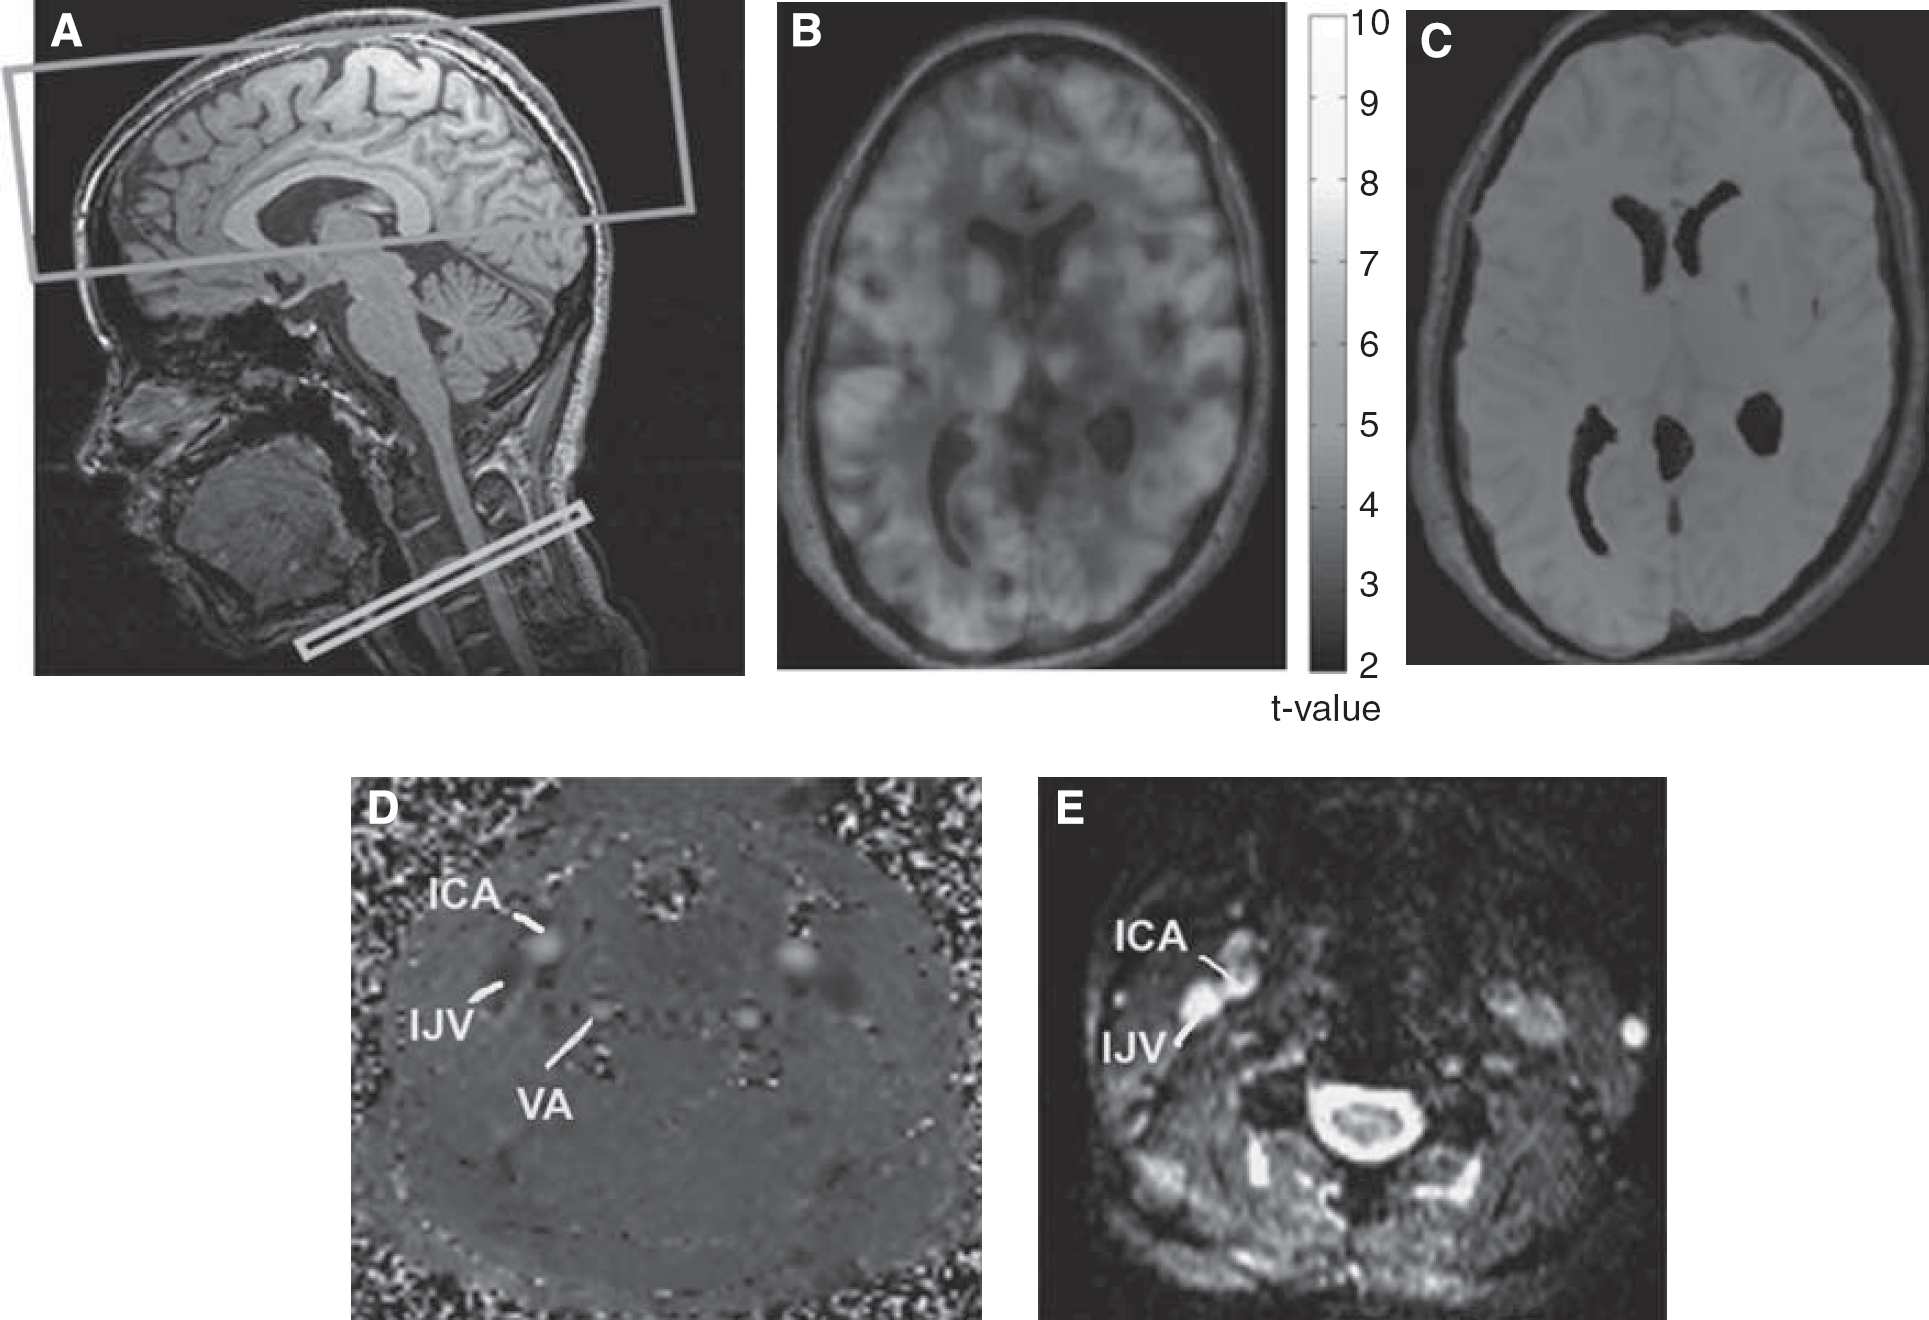

Typical PASL, internal jugular venous relaxometry, and internal-carotid PC flowmetry images are shown in Figure 1. The average estimated baseline venous oxygenation (

Mild and moderate levels of hypercapnia and hypocapnia were induced through the administration of mixtures of CO2 and medical air using the RespirAct breathing circuit (Thornhill Research, Toronto, ON, Canada), which provided computerized and independent targeting of PETCO2 and PETO2 (partial pressure of end-tidal oxygen) based on sequential gas delivery (Slessarev et al, 2007). This device provided high stability in PETCO2 targeting, while maintaining significantly more constant PETO2 levels than manual methods, both of which are crucial to the accurate quantification of CMRO2 changes due solely to PETCO2 changes. Each 12-minute PASL measurement consisted of three (60 seconds off:180 seconds on:120 seconds off) paradigms. In addition, two-dimensional cine PC flow data were obtained from five subjects in the internal carotid and vertebral arteries. These vessels account for the majority of cerebral inflow, and the corresponding PC acquisition (2.5 minutes) was used for cross-validation with the PASL data as a measure of global CBF. A finger pulse oximeter provided cardiac triggering and arterial oxygen data.